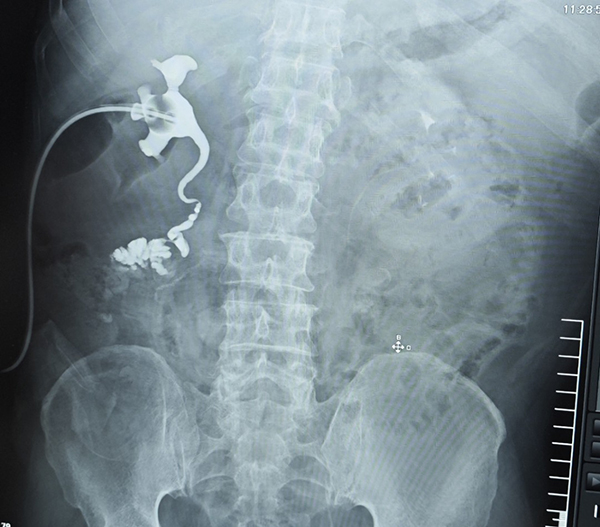

患者术前影像结果显示

手术历时整整12小时,一场与死神的殊死搏斗正式展开。手术由郑鑫团队和泌尿外科副主任王伟团队共同主刀,完成一系列的肾脏切取、移植肾修整、异体血管静脉延长、肾脏移植及输尿管重建等。严重的腹腔粘连让手术入路异常困难,腹腔镜下可见,腹腔内原本清晰的解剖结构被脓性渗出和炎性瘢痕完全掩盖,肠管粘连成团,输尿管已失去原有形态,仅残留糟烂的纤维组织。